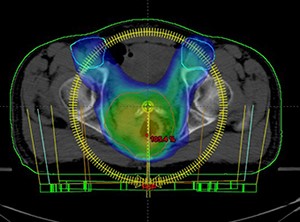

Procedimiento para el que se usa una computadora para crear una imagen tridimensional del tumor. Esto permite que los médicos administren la dosis de radiación más alta posible al tumor y, a la vez, protejan lo más posible de la radiación al tejido normal. También se llama radioterapia tridimensional y RTC-3D.

La radioterapia de intensidad modulada (IMRT, por sus siglas en inglés) es una modalidad avanzada de radioterapia de alta precisión que usa aceleradores lineales de rayos x controlados por computadora para administrar dosis de radiación precisas a un tumor maligno o áreas específicas dentro del tumor.

La VMAT es una forma de IMRT en la que la dosis de radiación se suministra al tumor mediante el giro continuado de 360º de la unidad de tratamiento. La distribución de la dosis se va depositando de forma precisa moldeándose y adaptándose a la forma del tumor. Las sesiones pueden contener uno o varios arcos para el tratamiento y detenerse y ponerse en marcha en algunas angulaciones determinadas.

La simulación/planeación es un procedimiento que se realiza previo a la administración del tratamiento con radiaciones, esto con el fin de asegurar la precisión del mismo, utilizando un tomógrafo y un sistema de posicionamiento por láser, una vez capturadas las imágenes, estas se procesan mediante programas de cómputo para realizar un modelo tridimensional del paciente y realizar reconstrucciones del tumor y los órganos de riesgo que se deberán de proteger. En este proceso el médico encargado se auxilia de un físico médico experto en el área.